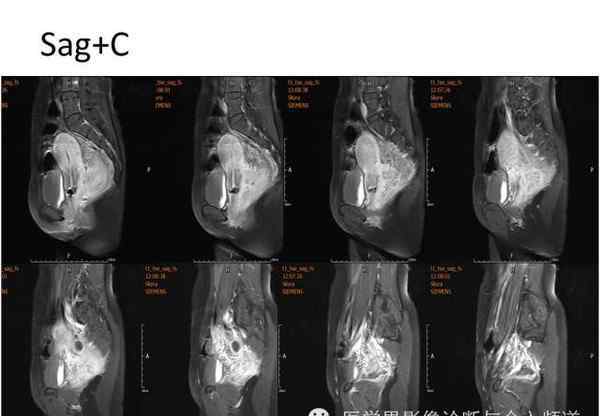

核磁共振平片扫描和增强扫描显示:

盆腔内可见弥漫性长T1长T2异常信号,FS-T2WI可见高信号,涉及直肠左前壁、直肠侧韧带和宫颈等。边界不清,盆腔可见条带状FS-T2WI高信号强度。注射钆喷酸葡胺后,病情明显加重。

腹腔镜探查:肝、胆、胃、胰、脾无异常,腹主动脉及肠系膜下动脉周围无肿大淋巴结,腹膜反射下直肠左前壁、直肠侧韧带及子宫颈坚硬,浸润成大小约5×5×4 cm的肿块,周围界限不清。